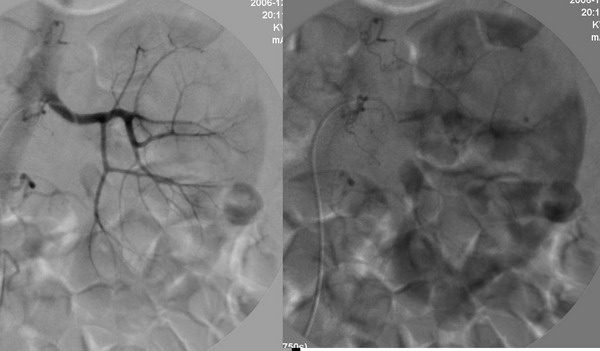

男性,45岁,因左输尿管与肾盂结合部结石住院治疗,经皮肾镜治疗失败后,改做开放手术.手术后3天出现血尿,5天保守治疗仍不能止血,申请肾动脉dsa,见下图片,发帖目的在于请各位分析判断出血部位.

介入治疗过程: